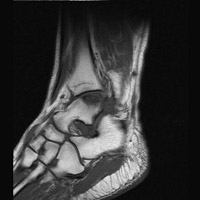

A | Lateral radiograph of the ankle. The abnormality is not seen. |